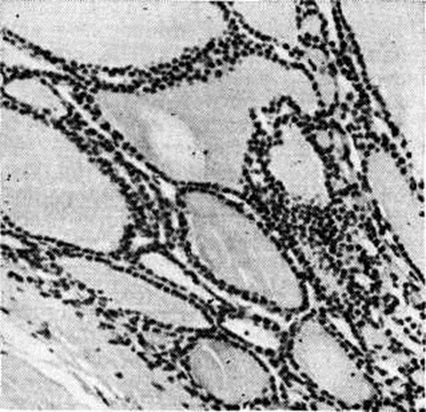

Патологическая анатомия характеризуется наличием трёх морфологический форм Зоб эндемический: разлитой (диффузной), узловой (нодозной) и смешанной (диффузно-узловой). В начале заболевания наблюдается диффузная форма с равномерным увеличением железы при неизменённых её контурах. Образование отдельных центров пролиферации приводит к развитию узловой или смешанной формы зоба. При узловой гиперплазии иногда обнаруживаются множественные узлы, различные по форме, плохо отграниченные от окружающей ткани, но сохраняющие тенденцию к росту. Микроскопически Зоб эндемический гетерогенен. Диффузный зоб представлен нормальной или микрофолликулярной тканью. В зависимости от функционального состояния фолликулы содержат базофильный, «густой» или только просвечивающий, почти прозрачный эозинофильный коллоид. В покое эпителий фолликулов кубический или плоский; в состоянии функциональной активности он становится высоким, светлым, образует сосочковидные выпячивания в полость фолликула (рисунок 1). В диффузных и узловых зобах встречаются трабекулярные и тубулярные структуры. Предполагается, что чем тяжелее эндемия зоба, тем чаще встречаются малодифференцированные формы паренхиматозного зоба (тубулярная и трабекулярная). Коллоидный зоб построен из фолликулов различной величины (макро и микрофолликулярный), богатых коллоидом, дающим положительную реакцию на РНК, белки и мукополисахариды. Комбинация фолликулов различной величины создаёт пёструю картину коллоидного зоба (рисунок 2 и 3). В зобах могут обнаруживаться инволюционные изменения (кровоизлияния, дистрофические процессы) с дальнейшим отложением в изменённых участках извести и холестерина. Паренхиматозные и коллоидные формы зоба могут трансформироваться в фиброзную форму с увеличением соединительнотканных образований. Солитарные аденомы (узлы) быстрее подвергаются различным инволюционным изменениям в связи с особым типом кровообращения. Узловой зоб может подвергаться малигнизации. Хотя нет достаточно убедительных данных о том, что Зоб эндемический чаще малигнизируется по сравнению со спорадическим, однако солитарная аденома в условиях эндемии зоба рассматривается как проблема онкологическая.